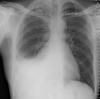

Which imaging is 1st line in acute asthma?

CXR - but doesn't delay management

What may a CXR in acute asthma show?

usually normal (may show hyperinflation or bronchial wall thickening)

What may a CXR show in COPD

* Hyperinflated chest (\>6 anterior ribs) * Bullae * Decreased peripheral vascular markings * Flattened hemidiaphragms